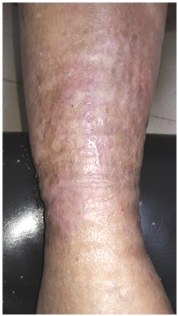

A las 48h de iniciar la terapia compresiva con vendas de baja elasticidad ya se observaba una adecuada contención del edema y, con ello, del líquido que drenaba la lesión (Figura 2).

Figura 2: Evolución tras 48h de Terapia compresiva.